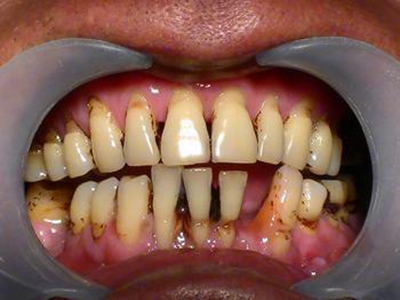

牙龈退缩上排多颗牙的牙根暴露图

牙龈退缩导致上排多颗牙齿的牙龈回缩,部分牙根暴露在外,伴有牙齿松动、口臭等症状,是由于牙周炎、局部受力过大等因素导致。